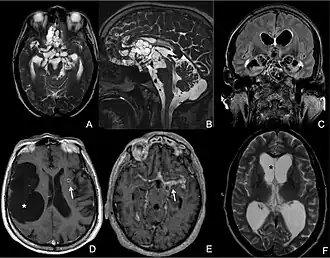

MRI of neurocysticercosis

Magnetic resonance image of a patient with neurocysticercosis demonstrating multiple cysticerci within the brain[1]

MRI of extraparenchymal neurocysticercosis

Different presentation patterns of extraparenchymal neurocysticercosis as revealed by brain MRI[36]